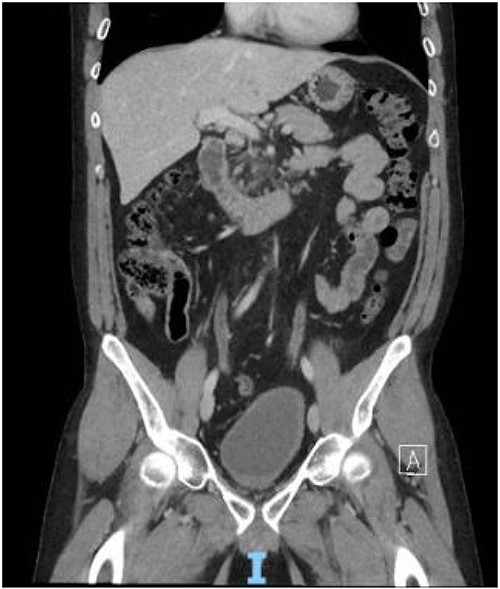

The patient presented to the ED 3 months later with urinary retention and pain; this was relieved with catheterization. A CT scan revealed that his tumor had slightly increased in size (Fig. 1). He had an AUA symptom index of 35. Due to the refractory nature of his obstructive symptoms, he was scheduled for a TURP 2 weeks later, which again revealed leiomyoma. He was kept on interval follow-up for the next 2 years. During that time his PSA was 1.13 ng/ml. Magnetic resonance imaging (MRI) pelvis 2 years later showed the mass appeared to communicate with the posterior bladder neck (Fig. 2). His baseline renal function kept worsening (Creatinine 1.4 mg/dl); at that time, the patient was counseled regarding his treatment options, and he opted for surgery which he was told may require the removal of the prostate with loss of ejaculatory and/or erectile function.

MRI Pelvis (contrast) June 2021: well-marginated complex solid, cystic, and septated pelvic mass with multiple sites of enhancement and restricted diffusion; the mass appears to communicate with the bladder neck.